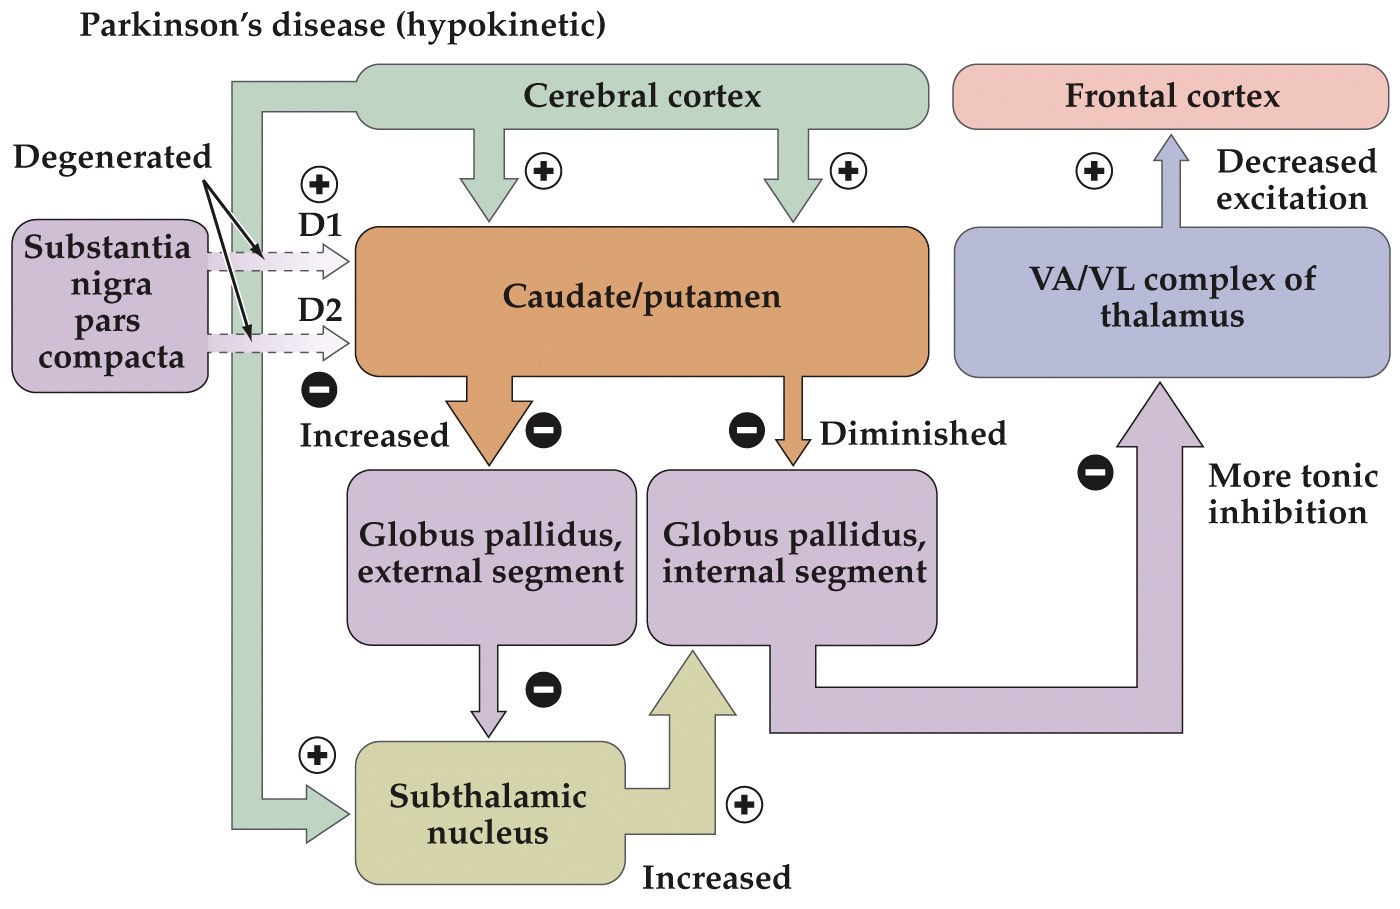

Motor behavior is determined by the balance between direct/indirect striatal outputs

- Hypokinetic disorders (decreased movement)

- Insufficient direct pathway output

- Excess indirect pathway output

Parkinson’s disease

- Due to the degeneration of dopaminergic neurons of the substantia nigra pars compacta

- Leads to tremors, slowness of movements, rigidity of extremities and neck, minimal facial expressions

- Slowly progressing disease

- Some success in slowing the progression comes from the use of Levadopa (L-DOPA)– gets converted to dopamine and gets to dopamine receptors in basal ganglia

Parkinson’s disease

Pathophysiology is the loss of nigrostriatal dopaminergic projections from SNc

Hypokinetic and hyperkinetic disorders summary

- Parkinson's– hypokinetic disorder. More tonic inhibition of thalamus and decreased excitation of frontal cortex

Parkinson's– hypokinetic disorder. More tonic inhibition of thalamus and decreased excitation of frontal cortex.